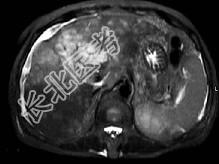

- 单项选择题根据所提供的图像,最可能的诊断是 ( )

A、胆管结石

B、肝癌

C、肝内多发囊肿

D、肝硬化

E、以上都不是